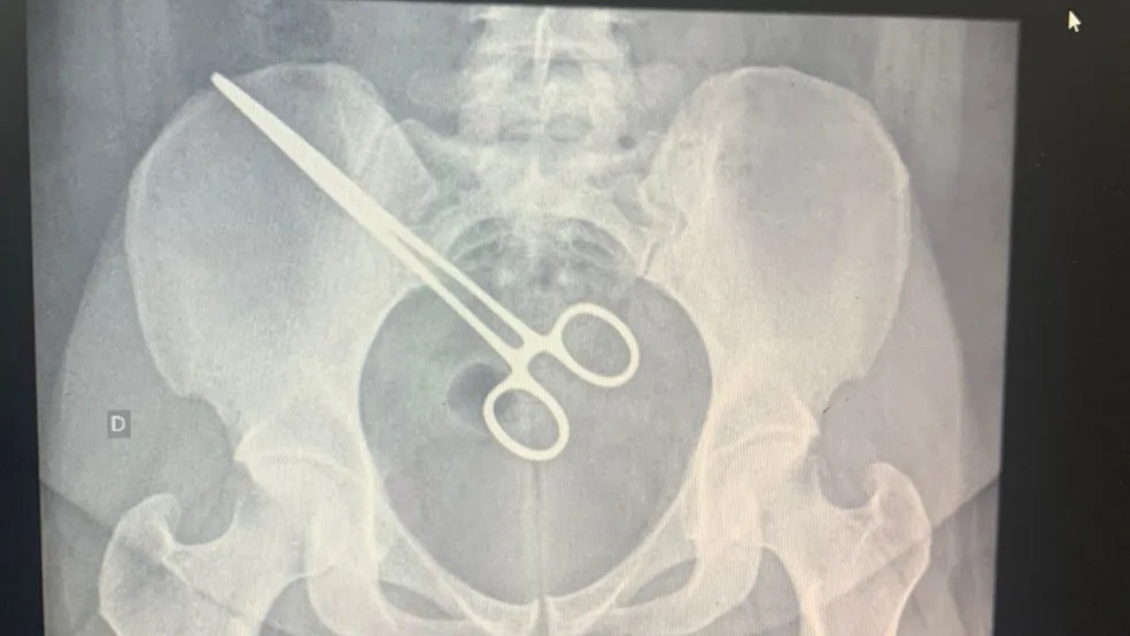

Una mujer de Brasil descubrió que tenía una pinza quirúrgica dentro de su pelvis luego que pasó por el detector de metales cuando fue a visitar a su marido en la cárcel.

Según informó el medio G1, la joven de 27 años se había sometido en septiembre a una cirugía para extraer un feto que se estaba gestando en las trompas uterinas, por lo que pasó más de dos meses con los utensilios en su interior sin saberlo.

Fue entonces cuando la mujer debió acudir a un hospital para que le retiraran el instrumento en una segunda cirugía.